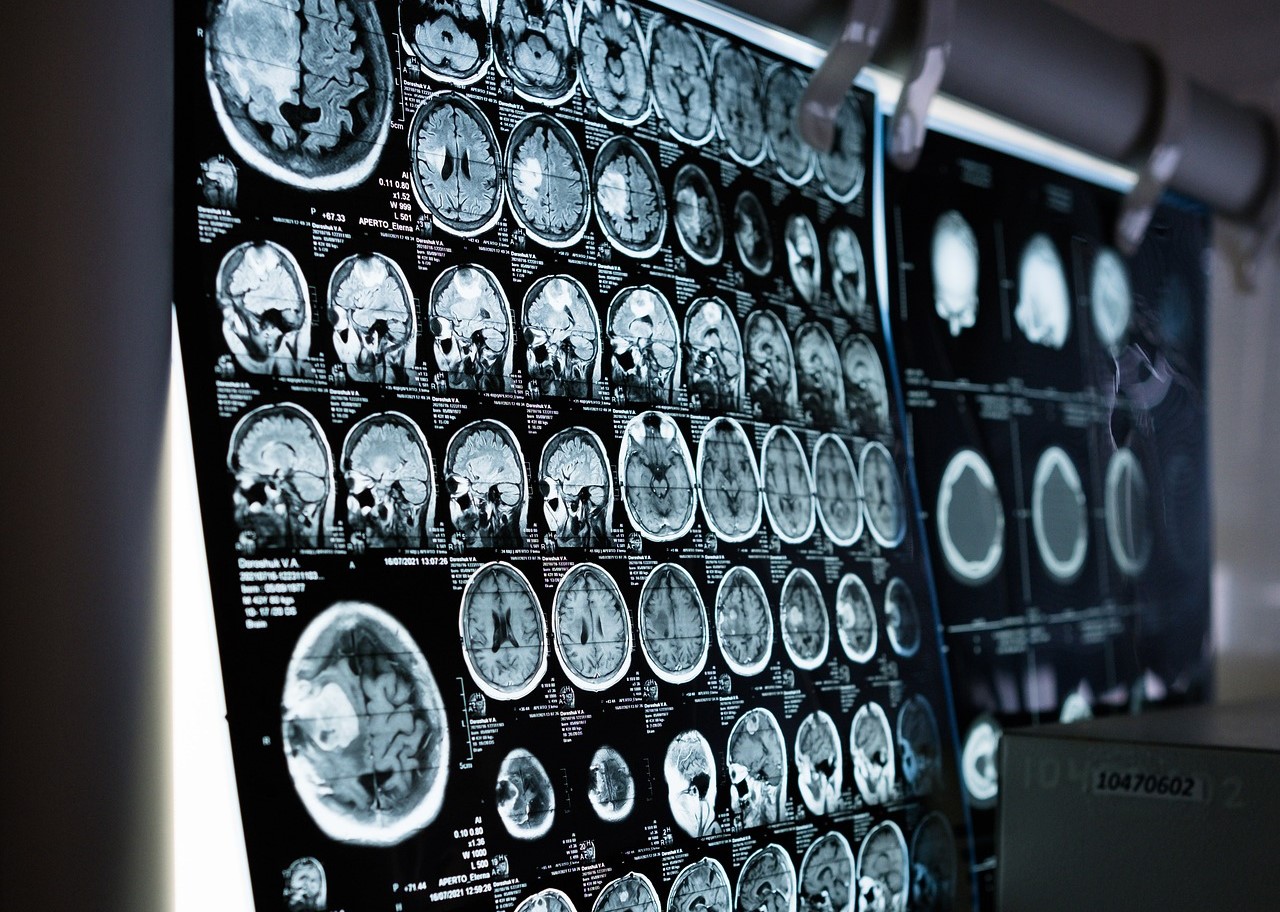

Ovaj lijek djeluje na uzrok Alzheimerove bolesti i djeluje na protein koji se stvara u tijelu zbog bolesti. Prvi je u nizu lijekova koji pomažu s ovom bolesti.

Ovaj lijek djeluje na uzrok Alzheimerove bolesti i djeluje na protein koji se stvara u tijelu zbog bolesti. To je prvi u nizu lijekova koji pomažu s ovom bolesti, a u budućnosti će možda biti još boljih opcija.